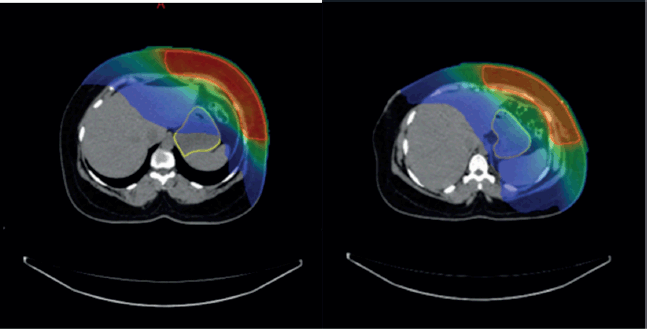

In contrast, no statistically significant difference was found in upper GI toxicity between 3DCRT and IMRT (p = 0.882) or between VMAT and IMRT (p = 0.083), indicating that IMRT does not significantly alter the toxicity profile compared to either 3DCRT or VMAT (Table 4) (Supplementary Figure 3a and b).

Supplementary Figure 3. (a and b): Isodose curves showing dose distribution between two RT techniques 3DCRT and IMRT.